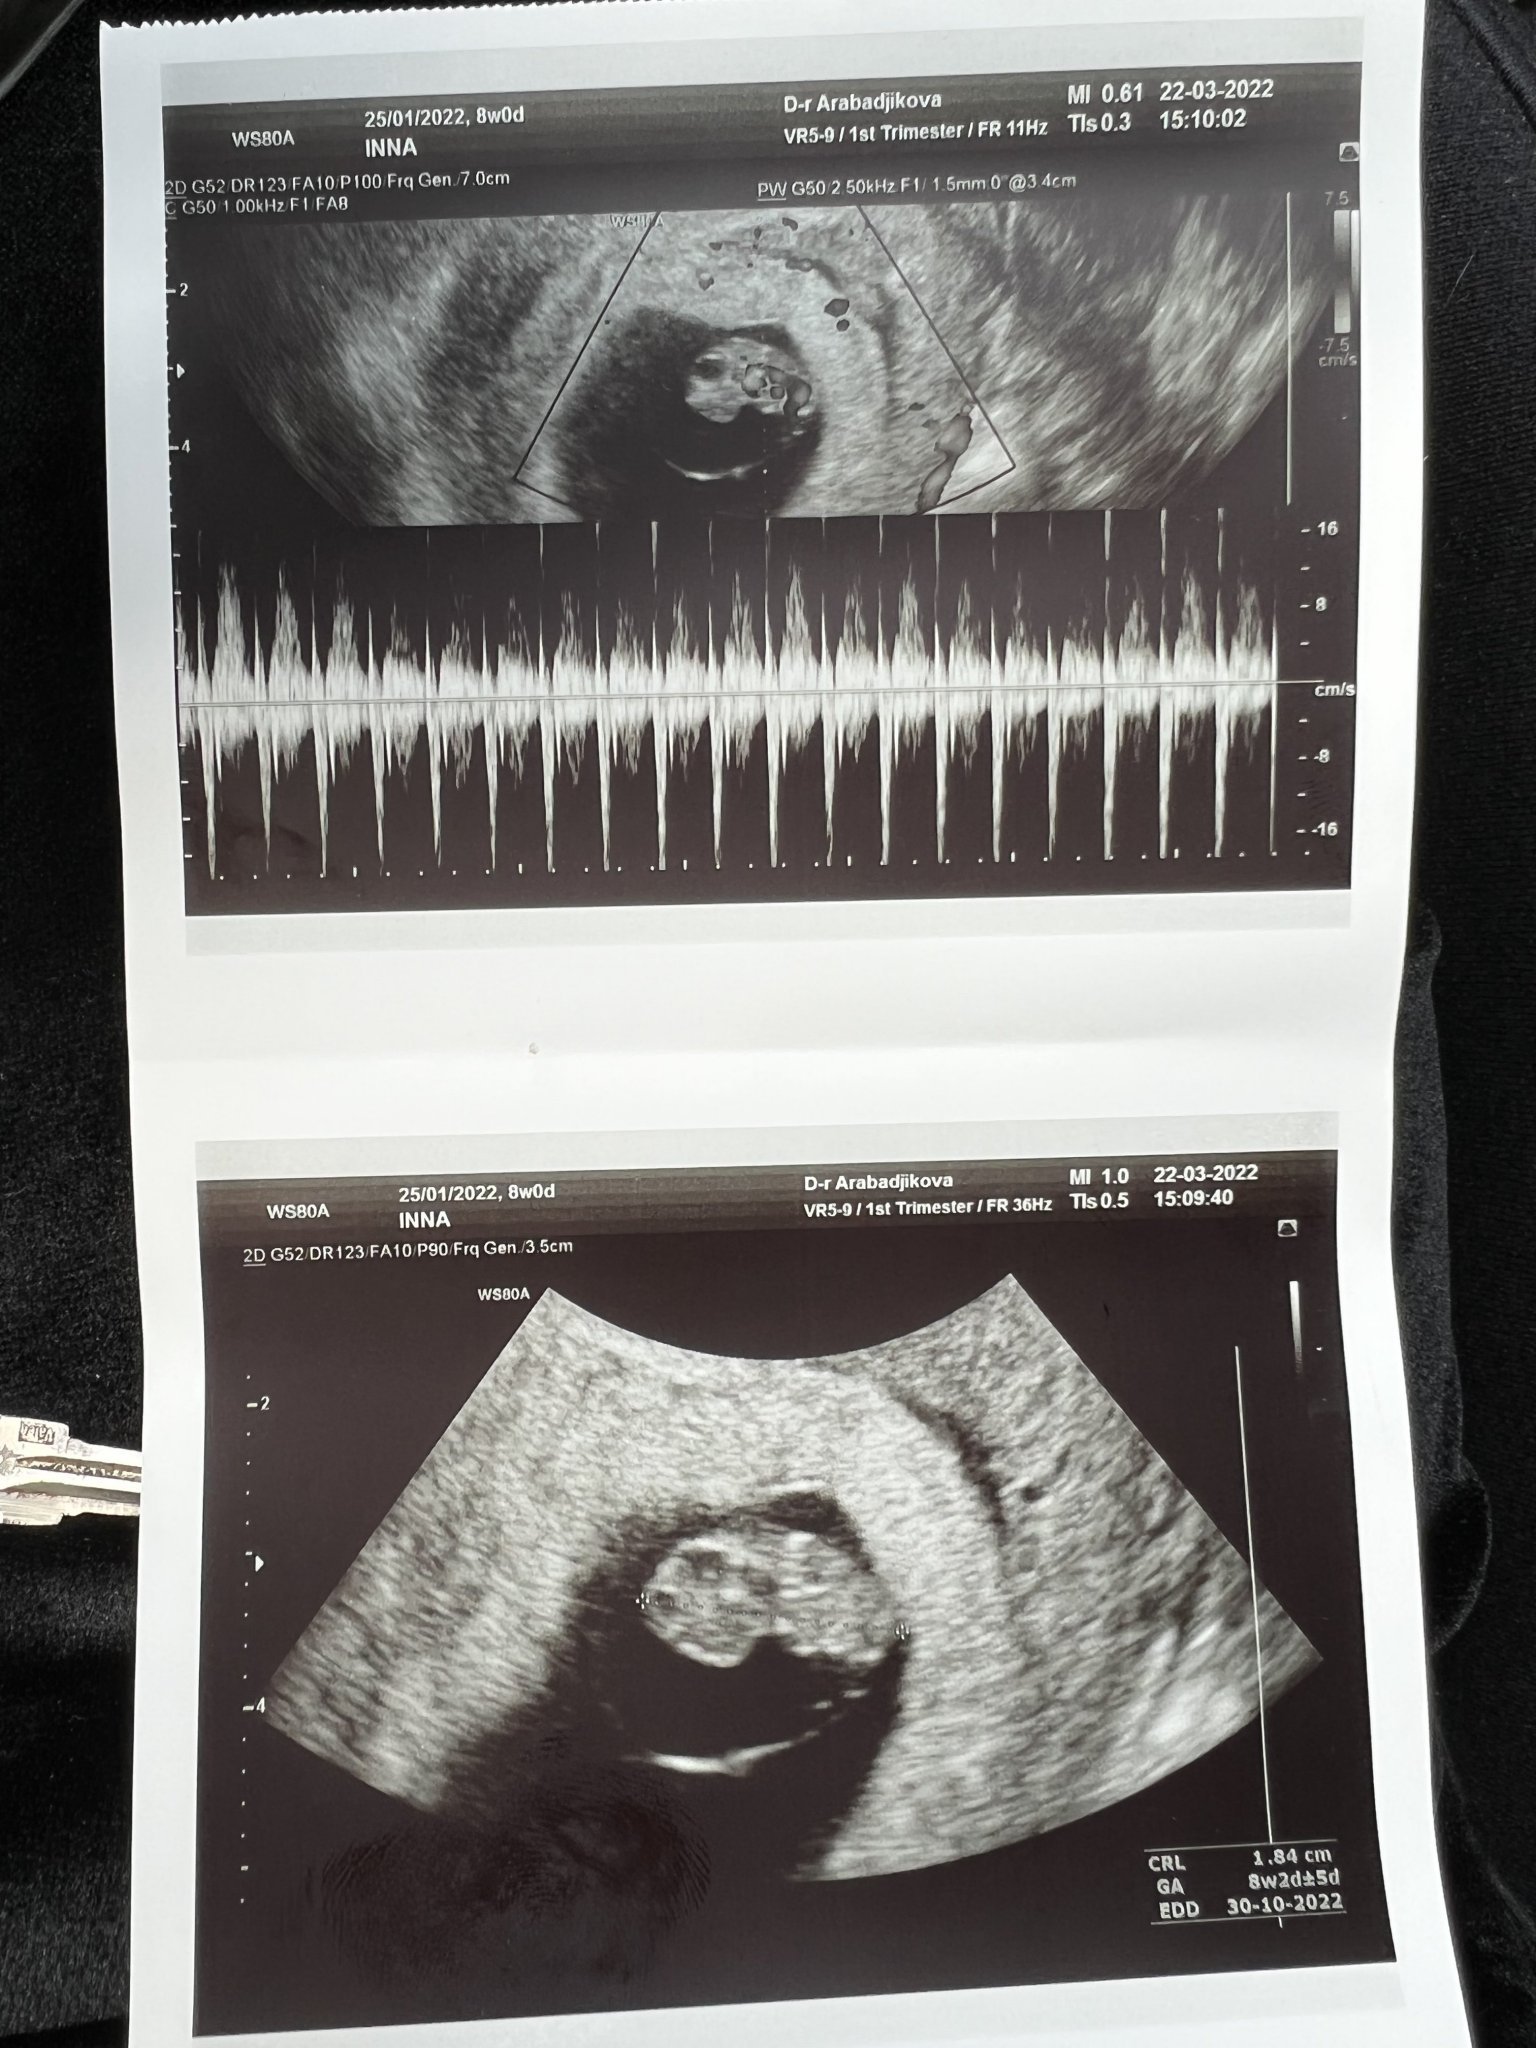

Днес ми беше първият преглед в 8гс и видях ембриончето, чух му пулса. Добре дошли на новите мами и съжалявам за тези, при които приключват бебешките емоции. Не се обвинявайте, бъдете спокойни и следващият път всичко ще е наред! И аз съм била от двете страни и знам какво е. Действително по-силно изразените симптоми означават, че ембрионът се развива. И на мен ми се гади по цял ден, понякога повръщам, лежа почти по цял ден, гърдите ми са подути и болезнени… Лекарката днес ме успокои, че това ще се случва най-късно до 12гс. Предписа ми едни хапчета за гадене “Емил”, но още не съм ги пробвала. Прикачам и снимка, защото някоя от вас искаше снимки с последен цикъл 25.01.22